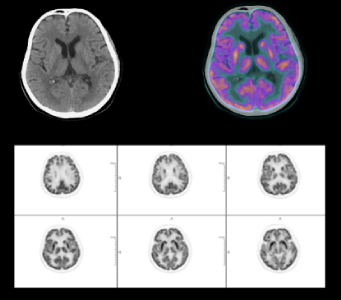

High Resolution Brain Imaging